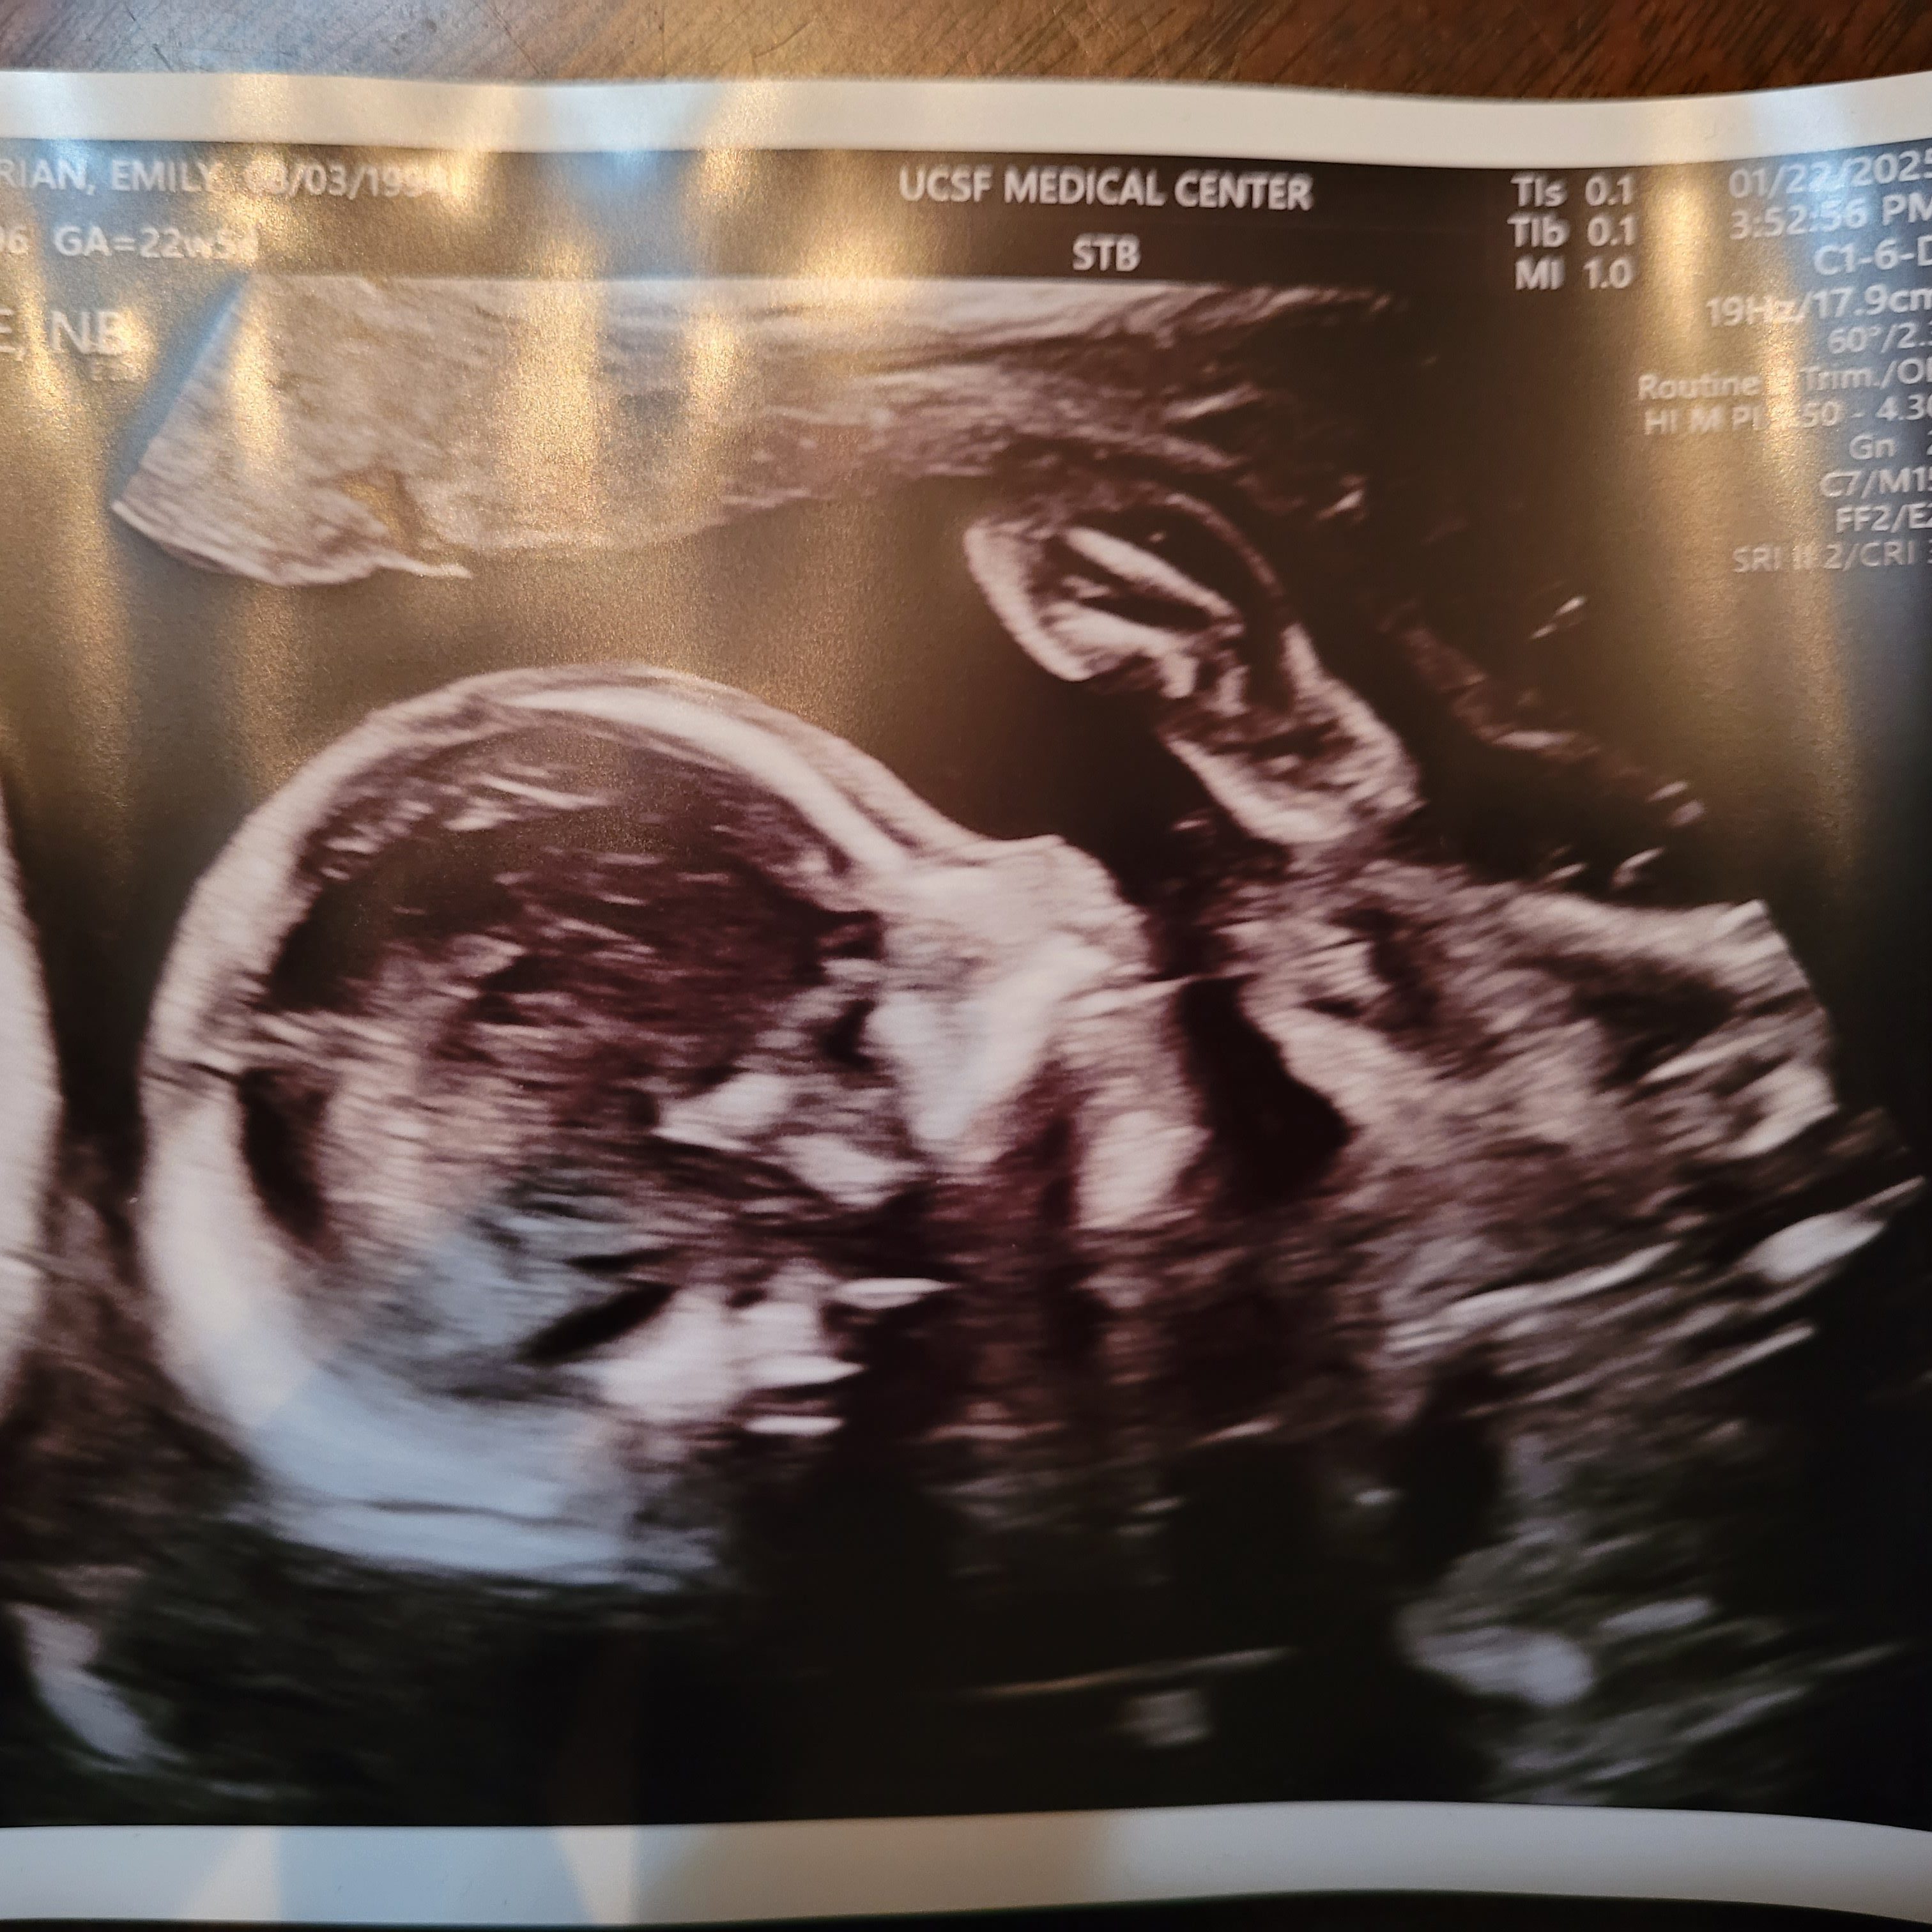

Last but most importantly: the anatomy ultrasound. During this hour-long appointment, the baby’s brain, heart, and spine are measured, and the toes and fingers counted to confirm they are all growing correctly.

The ultrasound tech commented repeatedly on the strange positions our baby was in, describing him first as a frog, with his legs pulled to his chest, and later as a taco, with his feet on either side of his head. So his nickname is now officially “taco-frog.”

We also got some pictures. My favorite is the one on the right that shows him covering his face with his hands, which is pretty cute. I think he looks a little like Emperor Palpatine too, but that is probably just me.